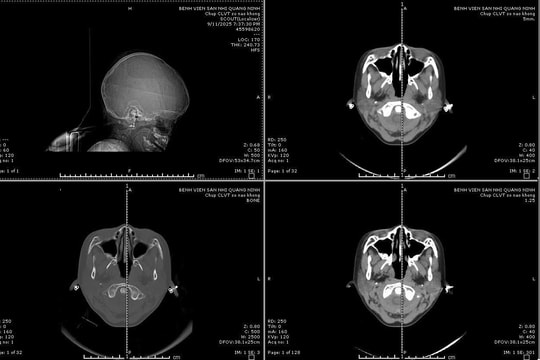

Kích hoạt "báo động đỏ" cứu sống bệnh nhi vỡ sọ phức tạp

27/09/2025 17:02

Bé gái 6 tuổi nhập viện trong tình trạng hôn mê do tai nạn sinh hoạt, đã được phẫu thuật cấp cứu và hiện sức khỏe ổn định.